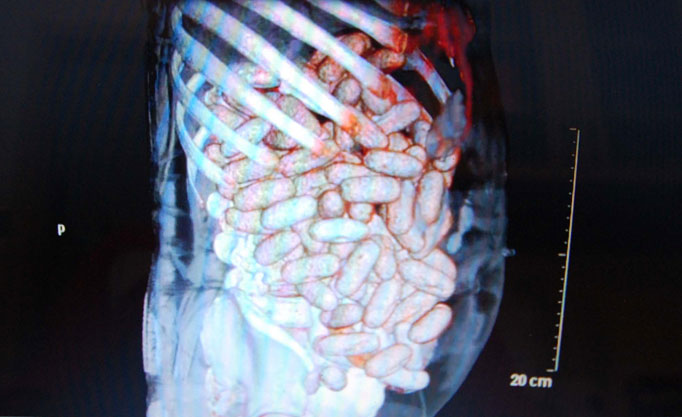

Một người đàn ông Anh đã bị bắt sau khi đang cố gắng buôn lậu 2 kg cocaine chứa trong dạ dày ra khỏi Brazil.

Người đàn ông 44 tuổi này đã bị bắt tại sân bay Congonhas tại Sao Paulo, Brazil sau khi chuẩn bị lên chuyến bay đến cộng hòa Senegal, ở phía Tây Châu Phi. Máy cụp X-quang đã cho thấy hình ảnh ở bụng của người đàn ông này có 89 viên ma túy có trọng lượng khoảng 2 kg.

Lượng cocaine đã được lấy ra từ dạ dày và ruột của người đàn ông tại bệnh viện sau khoảng 1 giờ bị bắt giữ vào ngày 8/11 vừa qua. Cảnh sát cho biết số ma túy này sẽ bán được gần 500.000 $ tại Châu Âu. Người đàn ông này sẽ có thể phải đối mặt với hơn 15 năm tù vì tội buôn lậu ma túy.